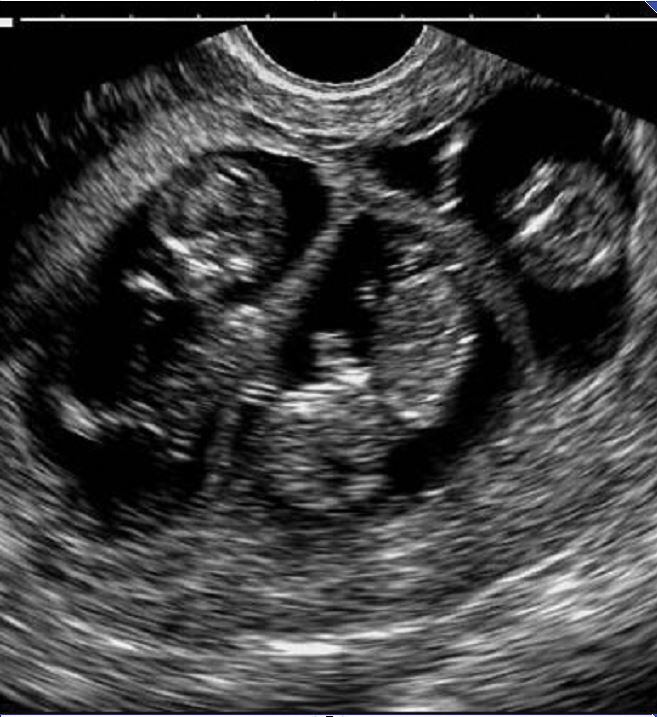

La inseminación artificial es una técnica que consiste en estimular la producción de óvulos en las mujeres, añadiendo, por vía oral o inyectada, dosis de la hormona natural llamada hormona estimuladora del folículo (FSH).

Gracias a esta estimulación, la mujer produce hasta 20 óvulos en un mes. Es entonces cuando un médico coloca en las trompas de Falopio los espermatozoides de su pareja. Allí se fecunda el óvulo y se forma el embrión.

“Es necesario realizar ecocardiogramas para corroborar el funcionamiento del sistema cardiovascular y una ecografía transfontanelar para ver el desarrollo del sistema nervioso central. También se requieren exámenes oftalmológicos por si el nervio óptico no se ha desarrollado del todo”, agregó.